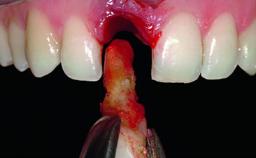

A healthy 37-year-old female patient was referred for a consultation on the replacement of missing tooth 21 with an implant-supported restoration. She stated that several years previously the tooth had been traumatically avulsed following a motor vehicle accident. The tooth was replaced with a three-unit fixed partial denture (FPD) immediately afterwards. Over time, she became disillusioned with the FPD and looked for a different option, including orthodontic therapy. She presented still in her orthodontic appliances, with the pontic sectioned free from the FPD but attached to the archwire. Her orthodontist felt that orthodontic treatment had been successfully completed, but nevertheless referred her before removing the appliances in case adjustments were necessary.

| Soft Tissue Grafting | Simultaneous |

| Bone Volume | Deficient horizontally, allowing simultaneous augumentation |